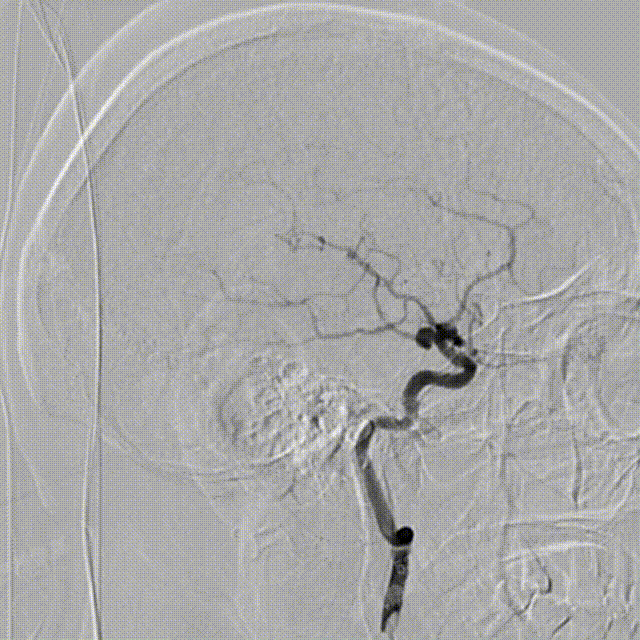

术中DSA造影:右侧颈内动脉工作角度及3D造影,显示右侧颈内动脉海绵窦段动脉瘤。

术中DSA造影:左侧颈总动脉3D造影及左侧椎动脉正位造影。

微导管超选入动脉瘤腔内,通过微导管使用弹簧圈填塞动脉瘤腔。